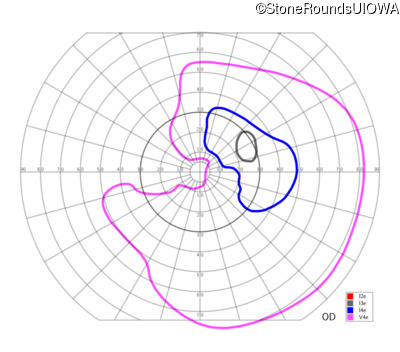

This 81 year old man began using a flashlight to read menus in his 40's. At age 75 his ophthalmologist noticed abnormal fundus findings and referred him to a retina specialist.

| OD | OS | ||